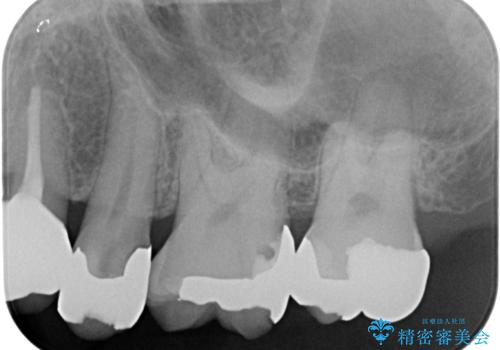

- 左上の歯が欠けたとの事で来院。

銀歯を除去し隣の歯も虫歯が見られたのでジルコニアクラウン、e-maxインレーで治療を行いました。